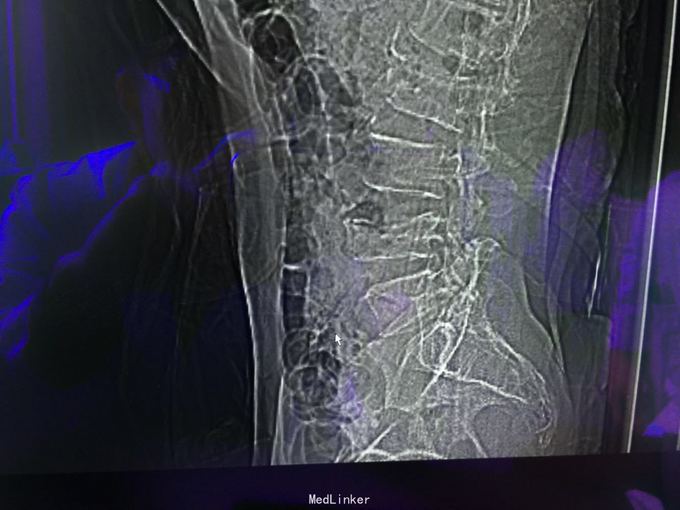

查体:左肾区叩痛,无皮肤隆起,未扪及肿块;腰椎压痛,活动受限,双下肢感觉存在,右小腿石膏托外固定,有踝关节明显肿胀,局部压痛活动受限,指端感觉血运可。 CT及X片:L2、L4椎体爆裂性骨折,L1-L4左侧横突骨折,右坐骨支骨折,右侧胫骨内、后及右侧腓骨外踝骨折,右足第1-4跖骨向外侧脱位及半脱位,伴近端斯脱性骨折。左肾挫裂伤,左肾重度积水,左肾周血肿。

诊断:右足lisfrance损伤,左肾挫裂伤;左肾周血肿,左侧输尿管结石伴左肾重度积水,L2、L4椎体骨折,L1-L4左侧横突骨折,右侧坐骨支骨折,右三踝骨折,全身多处皮肤软组织挫伤 处理:急诊行左肾探查,左肾切除术,择期行经后路腰2、4椎体骨折切开复位、椎公根螺钉内固定术+右内、外踝骨折切开复位内固定术,择期行右足lisfrance关节复位克氏针内固定术。